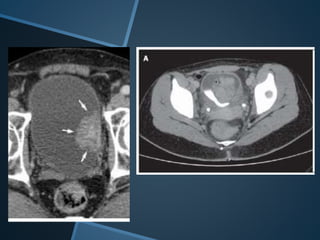

RTU VEJIGA

CA UROTELIAL

MUSCULO

INVASIVO

NEADYUVANCIA

RESPTA COMPLETA:

- TAC N

- CITOLOGIA

NEGATIVA

- RTU LECHO NEGATIVA

T2 30 PACIENTES Y SOLO 2 T3

30% ALCANZARON TO O RESPTA COMPLETA

7 PACIENTES CISTECTOMIA RADICAL

25 PAC. RECHAZARON CISTECTOMIA

SEGUIMIENTO 54 MESES

SOBREVIDA CANCER ESPECIFICA A 5 AÑOS 88%